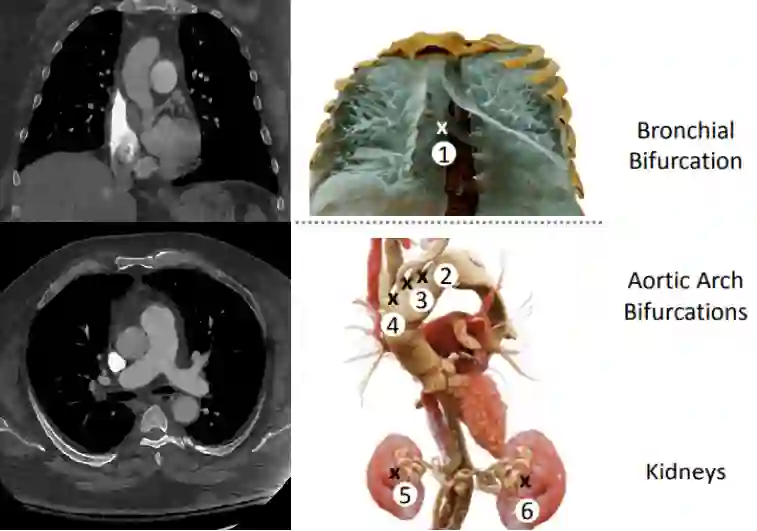

Pulmonary Embolisms (PE) represent a leading cause of cardiovascular death. While medical imaging, through computed tomographic pulmonary angiography (CTPA), represents the gold standard for PE diagnosis, it is still susceptible to misdiagnosis or significant diagnosis delays, which may be fatal for critical cases. Despite the recently demonstrated power of deep learning to bring a significant boost in performance in a wide range of medical imaging tasks, there are still very few published researches on automatic pulmonary embolism detection. Herein we introduce a deep learning based approach, which efficiently combines computer vision and deep neural networks for pulmonary embolism detection in CTPA. Our method features novel improvements along three orthogonal axes: 1) automatic detection of anatomical structures; 2) anatomical aware pretraining, and 3) a dual-hop deep neural net for PE detection. We obtain state-of-the-art results on the publicly available multicenter large-scale RSNA dataset.